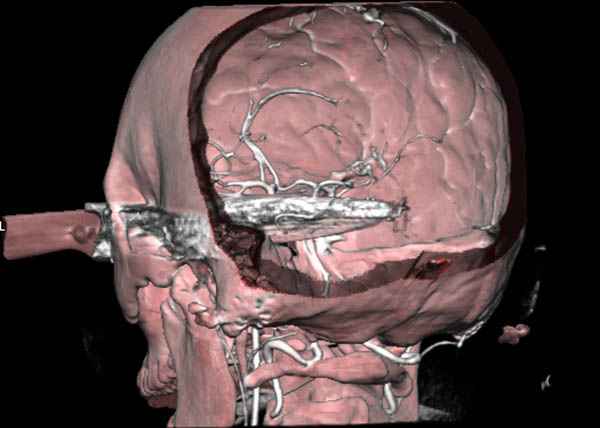

По протоколу сделаны все необходимые исследования: рентген, ангиограмма с 3Д реконструкцией, где обнаружили что все жизненно важные сосуды не задеты, даже некоторые "сидят" изгибаясь на ноже.

Одним махом нож удалить не удалось, пришлось раскачать и потом двумя руками удалили нож. Рана без кровотечения, обработана и зашита.